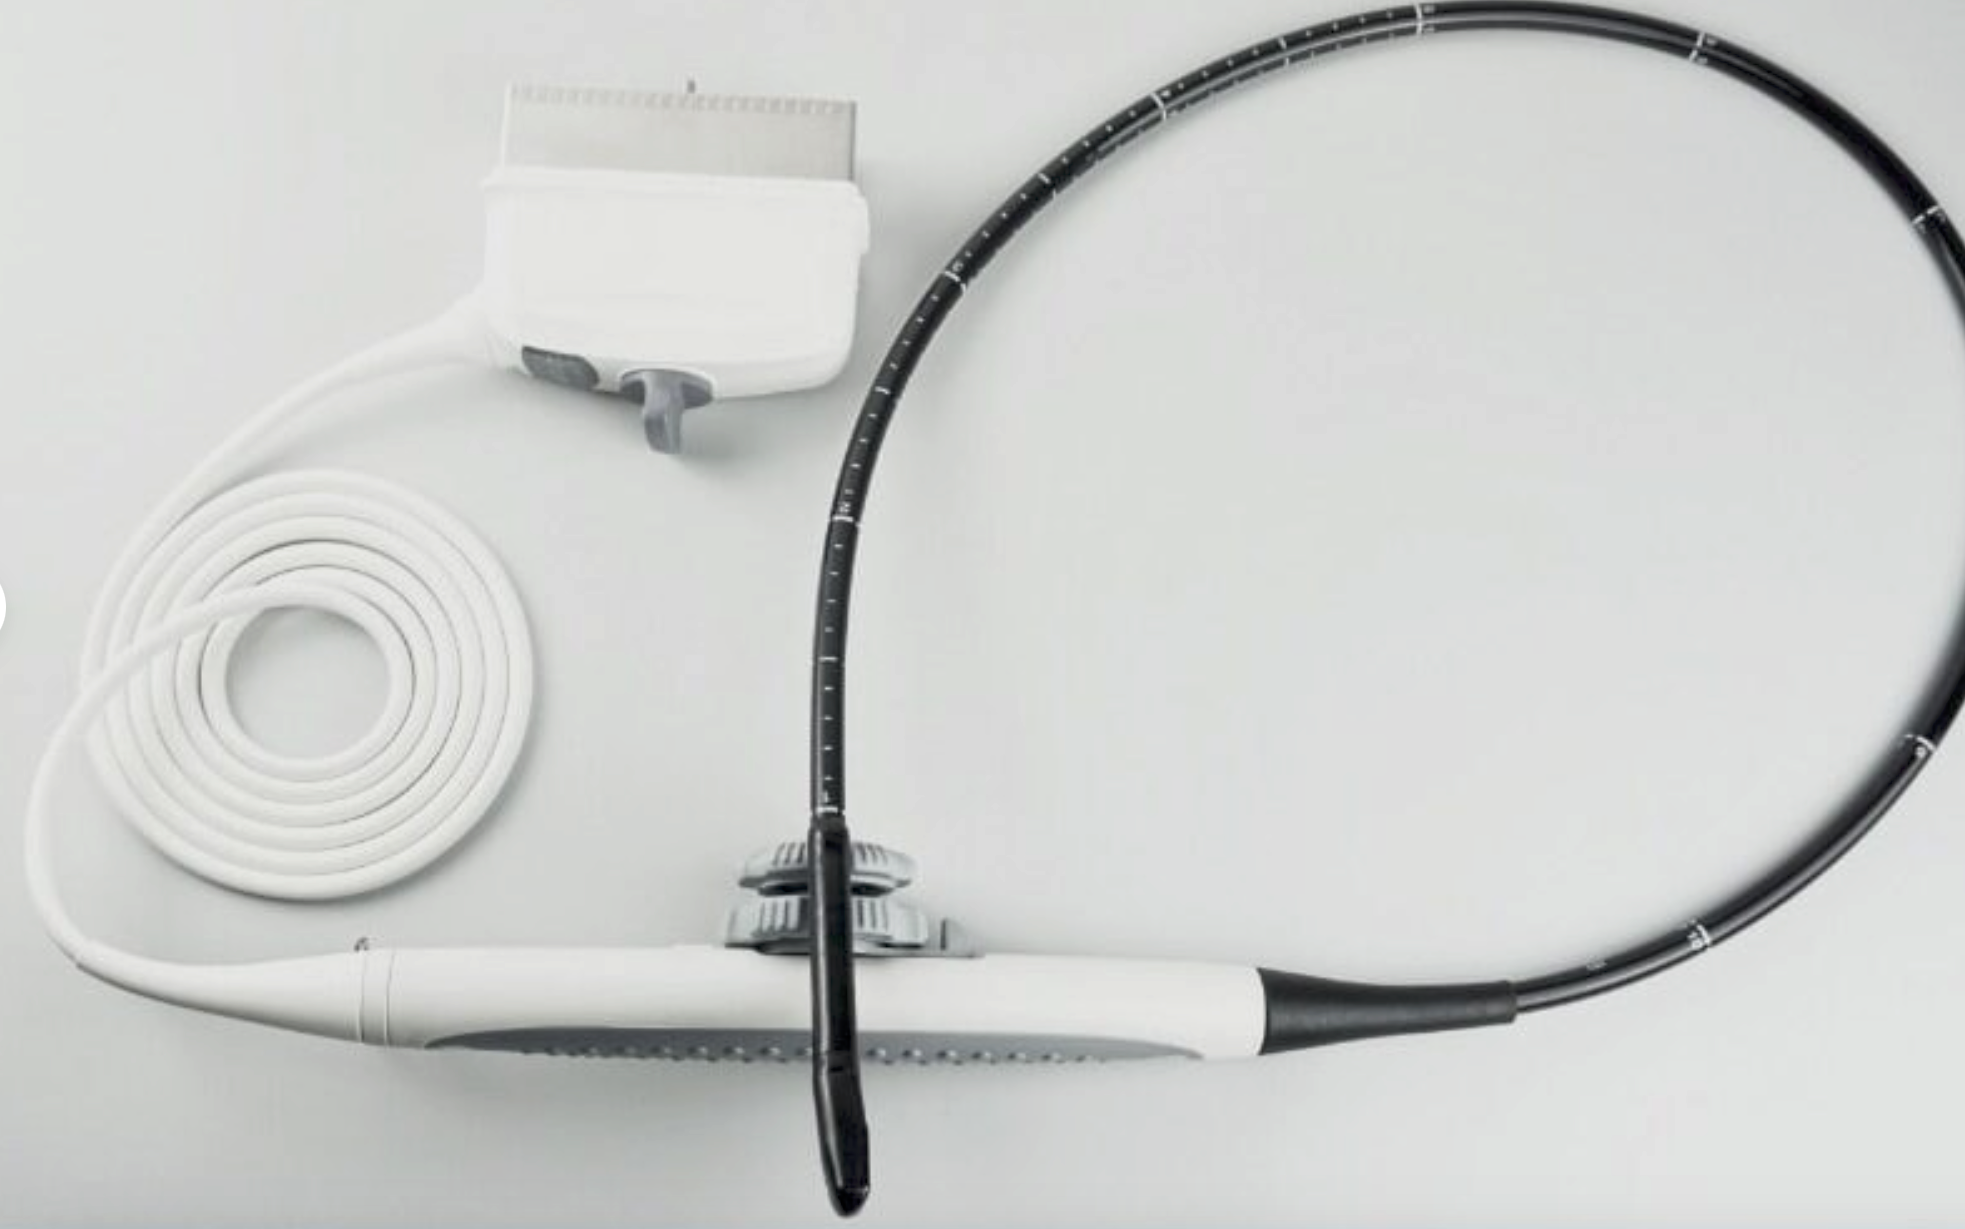

Probe 2: 7.5MHZ Transvaginal probe:gynecologic examination